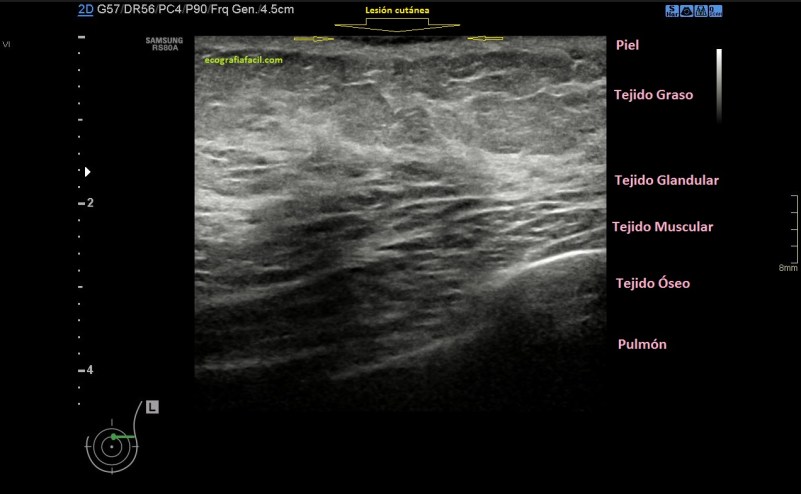

Imágenes:

1. Normalidad

En la imagen 1 tienes la normalidad, con anatomía, que te sirva para tener una base para que puedas valorar lo que ves en las imágenes siguientes. En la imagen 2 tiene una mama de una mujer joven, con el tejido fibroso ocupando gran parte de la mama, pudiera ser una mastopatía.